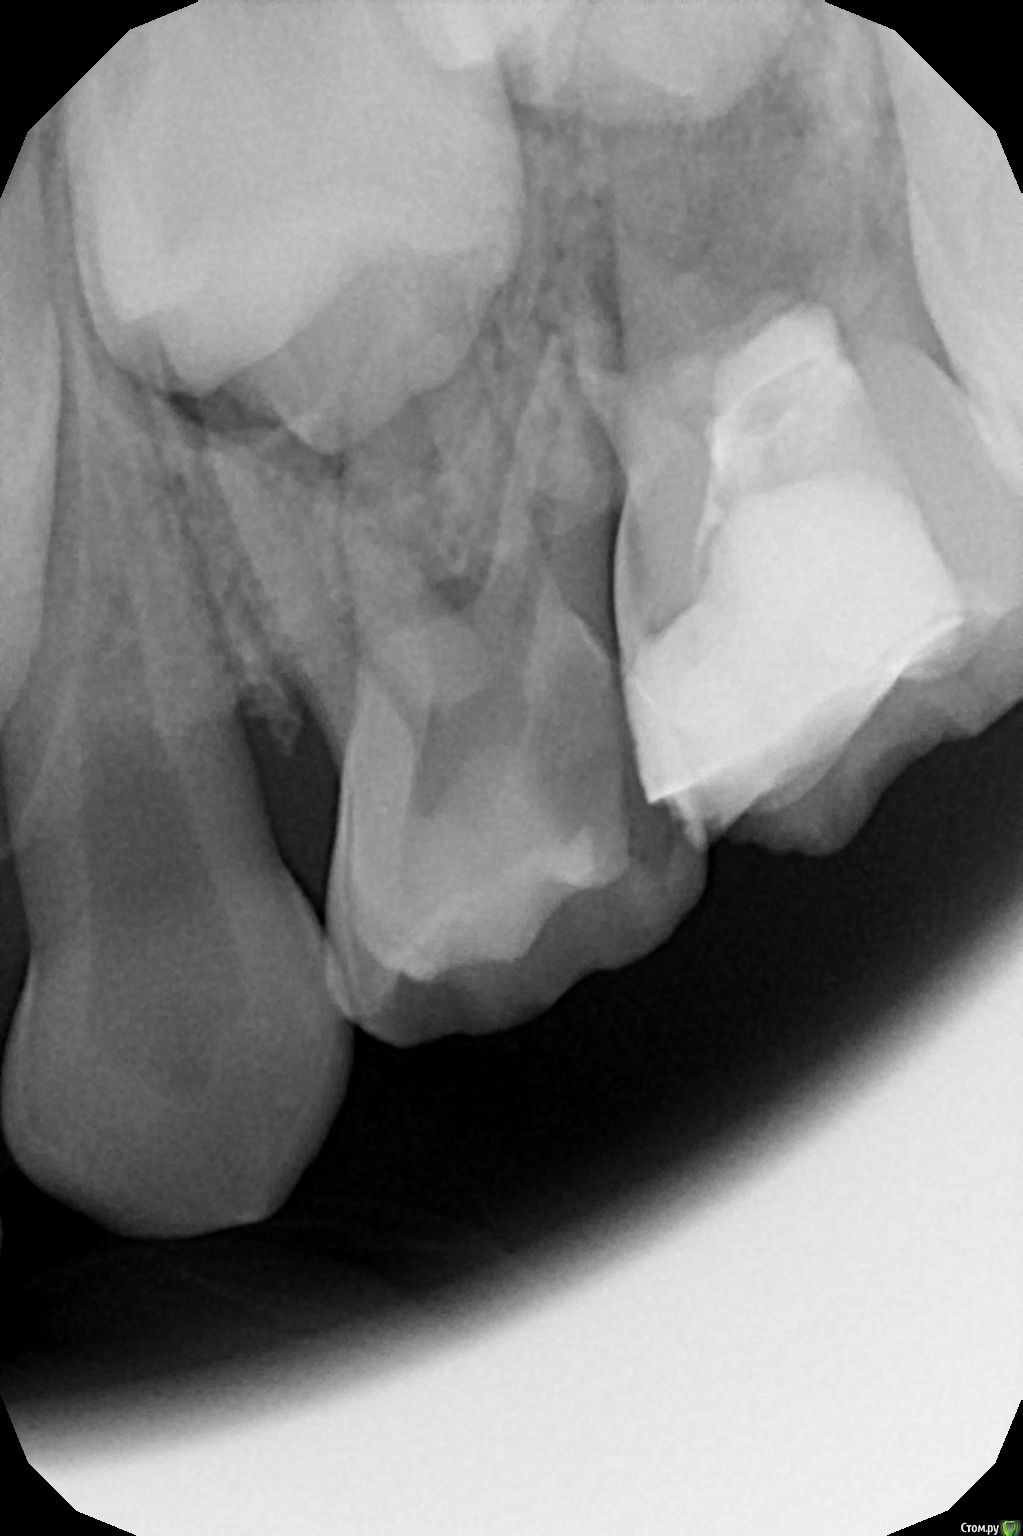

crown Опубликовано 9 июля, 2016 Поделиться Опубликовано 9 июля, 2016 Не знаю имел ли смысл поиск МБ2 и ДБ2, ну вообщем все 5 каналов в сборе) Правда ушло много времени и ребенок очень устал, что повлияло на качество обтурации. 3 Ссылка на комментарий

crown Опубликовано 15 июля, 2016 Поделиться Опубликовано 15 июля, 2016 Год назад пришли с периодонтитом 75, зуб был вскрыт в одной точке, до этого ходили полоскали, на рентгене почти полная резорбция, в бифуркации разрежение. Я не знаю зачем начал лечить его, вдобавок ко всему еще перфонул бором прям по середине (рукожоп). Вообщем "зарезорцинил" его, перфорацию и устья промыл гипохлоритом и закрыл триоксидентом. Вот пришли через год лечить соседний 74, а это стоит и не беспокоит, вот такой вот огрызок. Планируется на нижнюю челюсть заместительная пластинка, т.к. нет зубов на другой стороне, вот теперь не знаю удалять его или доживет? 3 Ссылка на комментарий